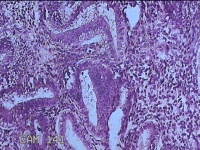

子宫腔赘生物

性别

女

年龄

33岁

临床诊断

子宫内膜息肉?子宫异常出血

一般病史

阴道流血12天。

标本名称

大体所见

灰白粉红色不规则肿物1.5x1.3x0.2cm一堆,表面糜烂。

图3